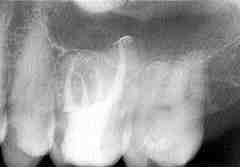

FIGURE 4 Lateral canals filled with sealer and/or gutta-percha is evident with the THC technique can be seen in the obturation of a plastic tooth A and clinically B.